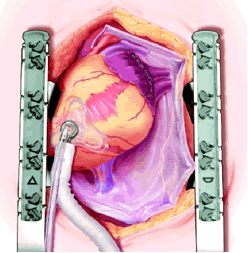

The pericardial sutures are withdrawn and the right hemisternum elevated by placing a folded towel under the lower right side of the sternal retractor, and an apical suction device (Urchin or Starfish [shown at left] Medtronic) attached to the cardiac apex. The heart is gently positioned similar to a ramus or high marginal coronary artery exposure. The left atrial appendage (LAA), and left sided pulmonary system should be in relatively clear view (LPA, LSPV, and LIPV).